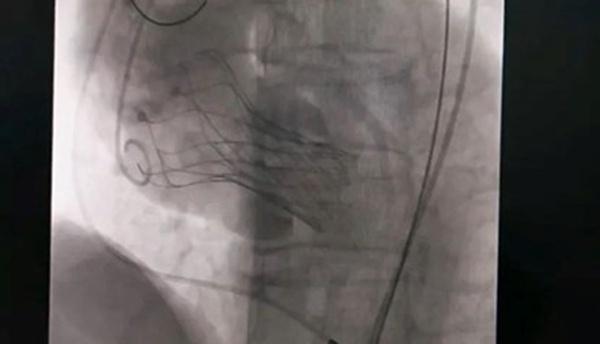

10月18日,該患者實施手術(shù),在新橋醫(yī)院專家的指導(dǎo)下,心血管內(nèi)科主任宋明寶帶領(lǐng)團隊把瓣膜置入心臟。

人工瓣膜置入中。重慶西區(qū)醫(yī)院供圖